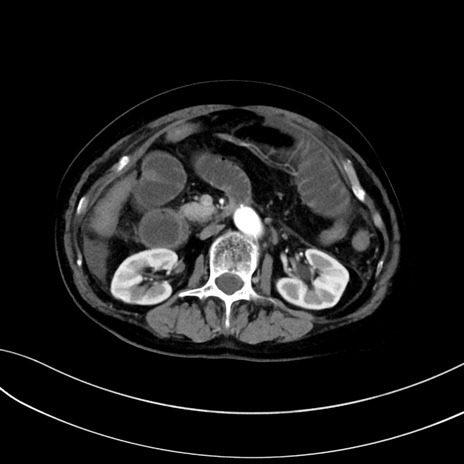

症例13 CT(横断像)1日半後

(冠状断像)1日半後